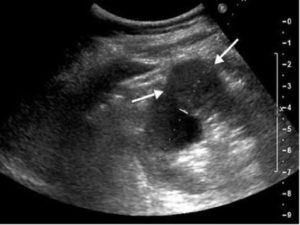

Первая диагностическая процедура, которую назначают при подозрении на опухоль почки – ультразвуковое сканирование. Оно точно определяет положение, размеры и структуру органа. При наличии опухоли размеры почек увеличиваются, изменяются их очертания и структура, точнее – эхогенность, то есть способность отражать и поглощать направляемые ультразвуковые волны.

Для того чтобы предположить диагноз рака почки, нужно знать, как он выглядит на УЗИ. Его эхографические признаки следующие:

- повышенная эхогенность (более высокая плотность);

- неровность контура, бугристость;

- неравномерность эхоструктуры (сочетание гиперэхогенных участков с анэхогенными);

- деформация чашечно-лоханочной системы (если опухоль расположена ближе к центру почки и сдавливает лоханку, чашечки).

На фото при цветном дуплексном картировании рак почки будет отличаться от доброкачественной опухоли обилием кровеносных сосудов, что является характерным признаком злокачественных образований.